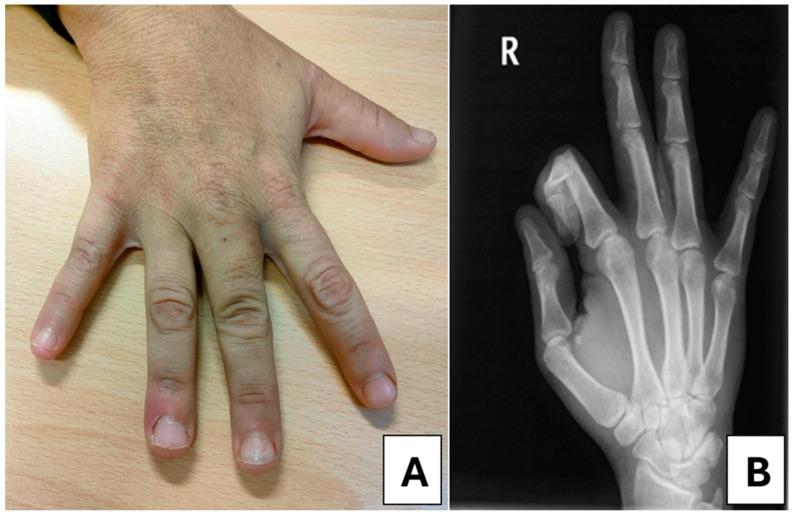

This report describes a 34-year-old woman with end-stage renal disease (ESRD) secondary to lupus nephritis, undergoing continuous ambulatory peritoneal dialysis (CAPD). She presented with a progressively enlarging calcified mass in the proximal phalanx of the third finger on her right hand, accompanied by functional impairment. Laboratory findings revealed persistent hyperphosphatemia (8.8 mg/dL), elevated parathyroid hormone levels (901 pg/mL), and low vitamin D levels (9 ng/mL), indicating significant disturbances to mineral metabolism. Imaging studies, including X-ray and whole-body 18F-Choline positron emission tomography/computed tomography (PET/CT), confirmed the presence of localized calcifications in the soft tissue of the proximal phalanx of the third finger on her right hand and parathyroid hyperplasia, respectively. Initial management included the optimization of phosphate binders and calcimimetic therapy, with the subsequent intensification of dialysis therapy. Transitioning to automated peritoneal dialysis (APD) with high-volume exchanges resulted in a notable improvement in biochemical parameters and the eventual remission of the calcified mass.

本报告描述了一名34岁因狼疮性肾炎继发终末期肾病(ESRD)的女性,正在接受持续性非卧床腹膜透析(CAPD)。她右手无名指近节指骨处出现一个逐渐增大的钙化肿块,并伴有功能障碍。实验室检查结果显示持续高磷血症(8.8mg/dL)、甲状旁腺激素水平升高(901pg/mL)及维生素D水平降低(9ng/mL),提示存在显著的矿物质代谢紊乱。包括X线及全身18F-胆碱正电子发射断层扫描/计算机断层扫描(PET/CT)在内的影像学检查分别证实右手无名指近节指骨软组织存在局限性钙化及甲状旁腺增生。初始治疗包括优化磷结合剂及拟钙剂治疗,随后强化透析治疗。转为高容量交换的自动化腹膜透析(APD)后,生化指标显著改善,钙化肿块最终消退。